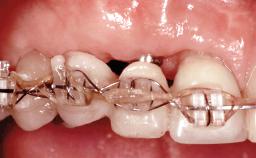

A 45-year-old woman was referred for management of an infection associated with two implant-supported crowns replacing the maxillary central incisors. Two tissue-level implants had been placed and restored with cemented single metal-ceramic crowns in those sites 4 years previously. The patient presented with a draining sinus (i.e. a pathological duct from an abscess cavity to a surface) 3 mm from the midfacial peri-implant mucosal margin of the maxillary right implant crown. She was in good general health, did not smoke, showed a good oral hygiene status, and had no history of periodontal disease. The implants were well positioned. While the patient was very satisfied with the appearance of her crowns, she had noted that the peri-implant soft tissue had receded since their insertion and was concerned about the possibility of further recession.